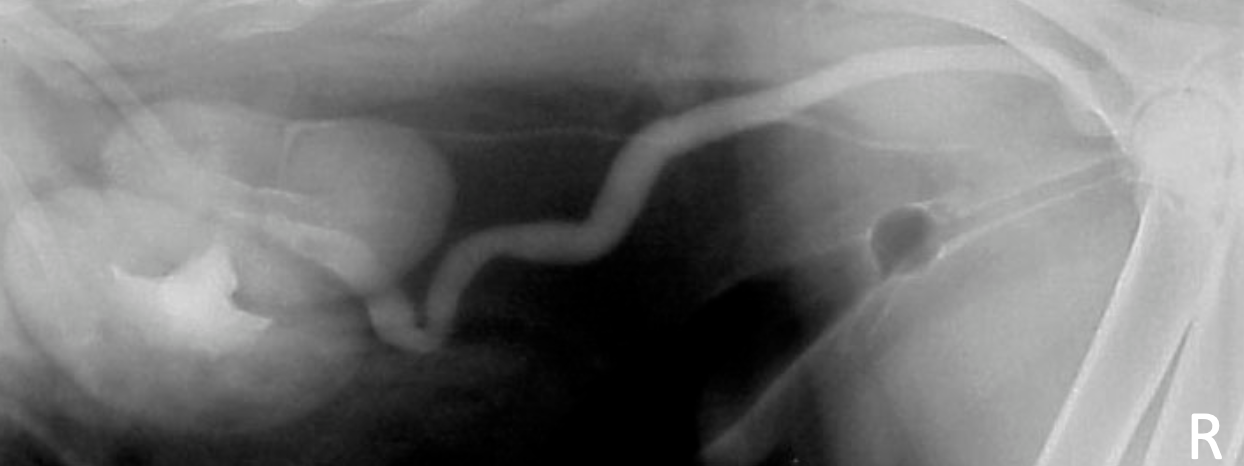

what combo of imaging modalities is the best way to view ectopic ureters

negative contrast cystogram (make bladder black) + EU (highlight ureters)

female dog with history of incontinence since birth

ectopic ureters

normal non-distended bladder

hydroureter

accumulation of contrast not in bladder

abnormal termination location of ureters

ureters and kidneys may appear normal - trace to abnormal termination site

± hydroureter/hydronephrosis if cause obstruction